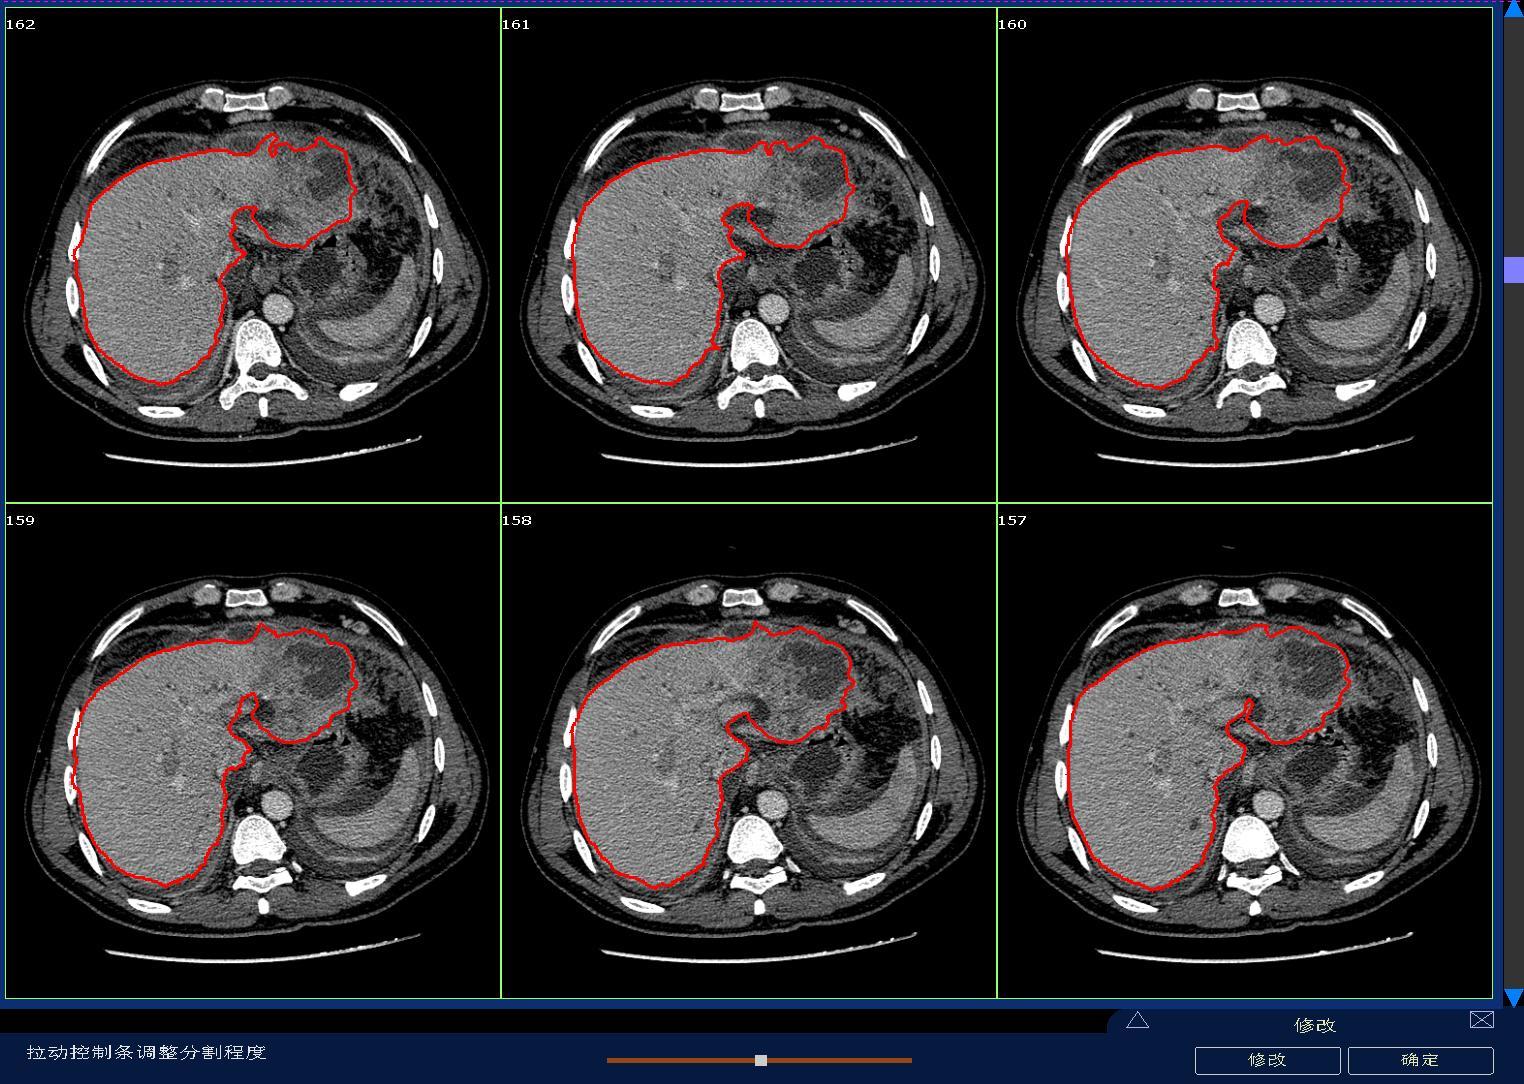

• Clinical application of three-dimensional visualization technology in assessing the spatial configuration of major hepatic vessels and liver lobar volume distribution

2026, 35(1):124-140. DOI: 10.7659/j.issn.1005-6947.250635

Abstract (93) HTML (137) PDF 3.82 M (171) Comment (0) Favorites

Abstract:Background and Aims The hepatic vascular and biliary systems exhibit substantial anatomical variability and complex spatial relationships, posing challenges for precise surgical planning based on conventional two-dimensional imaging. This study aimed to evaluate the clinical value of three-dimensional visualization in characterizing the spatial architecture of hepatic vasculature and bile ducts and to explore its association with hepatic volumetric distribution.Methods A total of 610 living liver donors and 158 patients with bile duct dilatation were retrospectively analyzed. Three-dimensional models of the hepatic artery, portal vein, hepatic veins, and bile ducts were reconstructed from contrast-enhanced CT images. Vascular and biliary anatomical patterns, spatial relationships, and their correlations with hepatic lobe and segmental volumes were systematically assessed.Results Three-dimensional visualization enabled intuitive and comprehensive depiction of hepatic vascular and biliary anatomy. Distinct portal vein configurations were associated with significant differences in regional liver volume distribution, with an increased proportion of the right posterior lobe observed in patients with specific portal vein branching patterns. The presence of an inferior right hepatic vein with a diameter ≥5 mm was also associated with a larger right posterior lobe volume. Analyses of extrahepatic and intrahepatic spatial relationships revealed relatively consistent positional patterns between the right hepatic artery, portal vein, and bile ducts, and a significant correlation was observed between the spatial courses of the right hepatic artery and the right posterior bile duct.Conclusion Three-dimensional visualization provides accurate preoperative assessment of hepatic vascular and biliary anatomy and clarifies complex spatial relationships and their volumetric implications. This technique offers critical anatomical support for precision hepatobiliary surgery and liver transplantation.